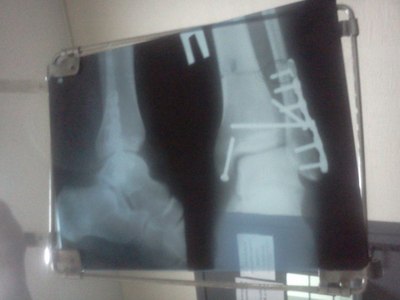

И мне недавно поставили. Точно такую же штуку как на рентгене у автора.. И нога так же левая, и даже средний болт так же торчит с другой стороны=)

Вот только на второй кости еще два шурупа. Очень хочется уже поскорее начать нормально ходить. Ну что ж, всем "киборгам" скорейшего выздоровления=)